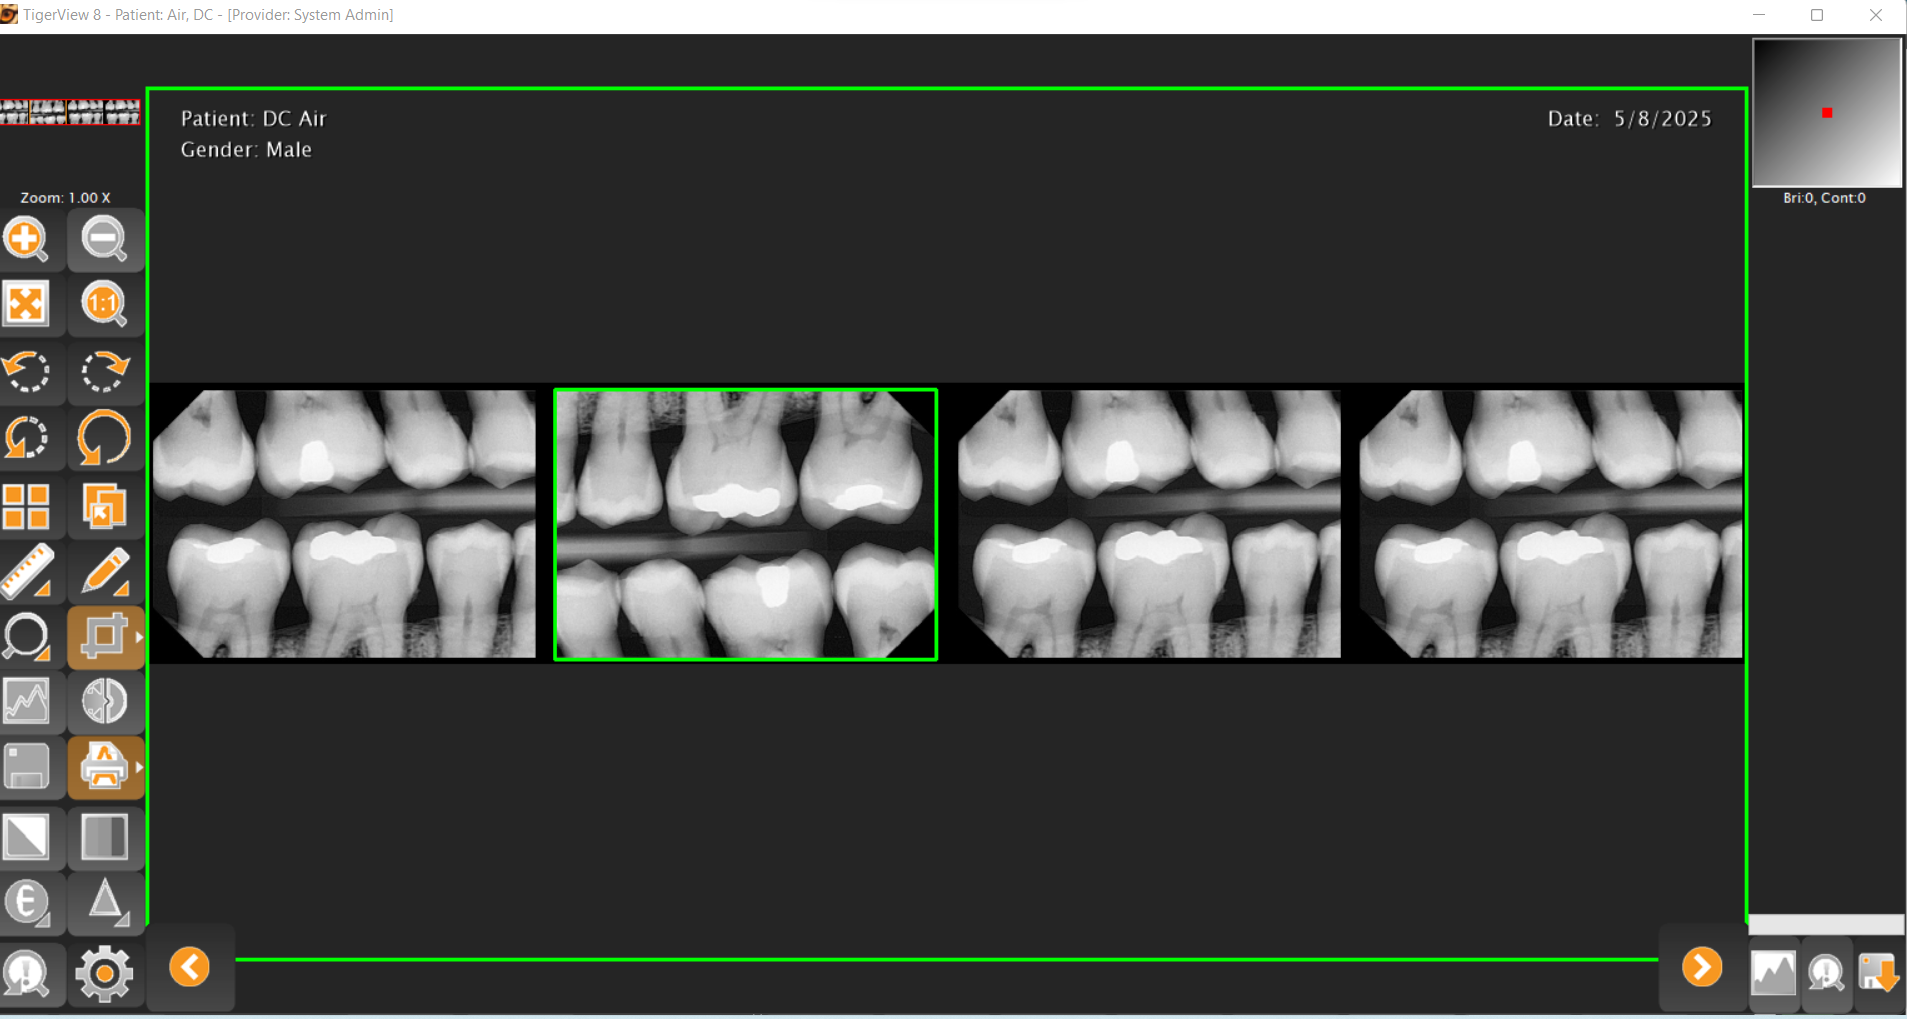

The TigerView Imaging Base Package is the foundation of a modern dental imaging workflow. Designed specifically for dental practices, TigerView allows you to capture, store, view, and share all diagnostic images — including digital X-rays, panoramic images, intraoral camera photos, and scanned film — from a single, unified platform.

Built with a user-friendly interface and DICOM 3.0 compliance, TigerView supports a wide range of imaging hardware from multiple manufacturers. This flexibility allows your practice to choose the equipment that fits your needs without being locked into proprietary systems. All images are stored in one database, making it easy for your team to access, compare, and present images across multiple exam rooms.